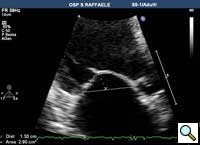

In absence of controlled clinical trial data which are forthcoming from the EVEREST II randomized study, the indications for the MitraClip therapy are currently based on registry experience and will evolve as the technique improves, experience is growing and the data to demonstrate efficacy and safety becomes available. At this time, the best indication for the MitraClip therapy is for symptomatic patients with clinically significant functional or degenerative MR who are at high or increased risk for open heart surgery. From a pure technical standpoint, the procedure so far has only been demonstrated in a subgroup of patients with specific anatomical characteristics which are summarized below and shown in Figure 3. Anatomic suitability is assessed by transesophageal echocardiography, and mitral regurgitation should originate from the central portion of the valve involving the A2-P2 segments, since the device is not ideal to work in the commissures at this time; the mechanism of MR can be either a prolapse/flail or MR due to restricted leaflet motion unrelated to rheumatic disease; the separation between the two leaflets at the site of regurgitation should be limited; severe annular dilatation and/or severe calcification should be absent or is relevant. In case of flail, the flail segment width should be less than 15 mm, and the flail gap less than 10 mm. Figure 4 is a 3D echo image of a patient with posterior leaflet prolapse selected for MitraClip therapy. In case of functional MR, the leaflets should have a minimal residual tissue available for coaptation with the MitraClip device. Figure 5 shows 2D color Doppler jet extension over the coaptation line at TEE short axis transgastric view, while Figure 6 shows the tenting area and the coaptation depth of a patient undergoing MitraClip implant.